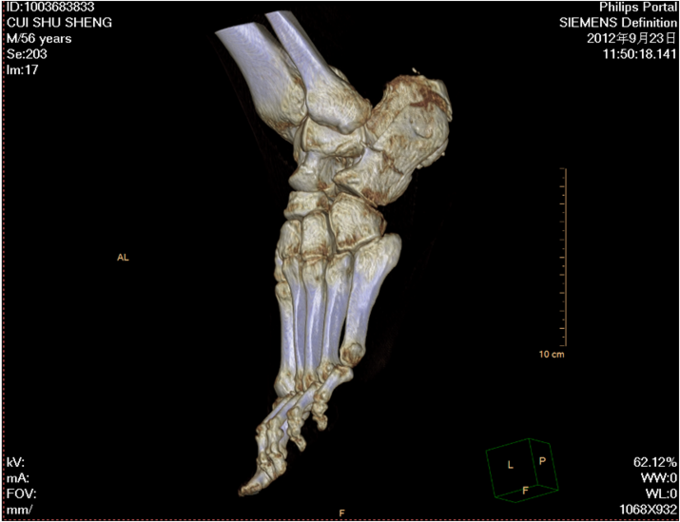

主 诉:摔伤左足跟部疼痛活动受限1小时。现病史:1小时前在自家干活时不慎从2米高梯子上摔下,当时患者意识清醒,无法站立,左踝部疼痛、肿胀、活动受限;被急送往中国医科大学附属盛京医院,经急诊医师会诊后,建议住院治疗,患者及其家属今为进一步治疗,要求入院,我科以“左踝部骨折”为诊断收入我科;患者伤来无发热、无头晕、恶心呕吐,无呼吸困难,既往饮食睡眠可,大小便正常;

左踝部肿胀明显,压痛阳性,左踝部活动受限,可闻及骨擦音及骨擦感;患肢皮肤感觉较健侧无明显异常,足趾可活动,足背动脉可触及; 望:神志清,精神尚可,面色微黄,营养良好,体型中等,舌红,苔薄黄;闻:语声重浊,呼吸均匀,未闻及特殊气味;切:脉弦紧。

中医诊断:左跟骨粉碎骨折(气滞血瘀) 西医诊断:左跟骨粉碎骨折 治疗:手术治疗 中医辨证论治:根据骨伤科三期辨证理论,早期因瘀血停滞影响骨痂生长,故以活血化瘀,消肿止痛为主,应用桃红四物汤;中后期补益肝肾,补气养血,应用愈骨胶囊等药物应用。现患者属于骨折早期,可运用桃红四物汤加减对症治疗,方药如下: 桃仁10g 红花10g 当归12g 川芎12g 赤芍12g 穿山甲6g 柴胡12g 黄芩10g 香附12g 延胡索15g 续断15g 生地12g 甘草6g 3剂 用法:每日一剂,水煎服400ml,分早晚两次温服。 中医调护:避风寒,慎起居,忌生冷,畅情志。